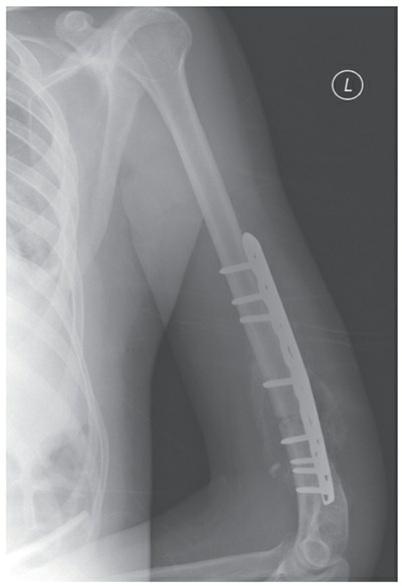

EXAMINER: "Good morning, candidate. You are presented with a 35-year-old male patient who reports left arm pain after slipping and falling on a flexed elbow at work. Here is his initial radiograph."

❓ EXAMINER: "Please interpret the X-ray image for me. Describe your findings and classify the type of fracture shown for this patient."

Certainly, Examiner. The X-ray image (Figure 1) reveals a displaced fracture located in the middle third of the left humerus. There are no signs of dislocation in the left shoulder or elbow joints. Clinically, the patient presented with focal pain and deformity in the left middle humerus, with no pain at the shoulder or elbow joints. Based on these findings, the fracture can be classified as a mid-shaft humerus fracture.

🔍 Click to enlargeFigure 4: Plate and screw fixation of a distal third humeral shaft fracture. - **Intramedullary Nailing (IMN):**